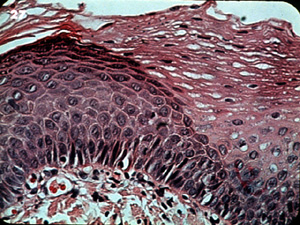

La apariencia microscópica típica

de la queratosis benigna revela formación de queratina aumentada y

acantosis del epitelio. Las células son uniformes y ninguna displasia

está presente. |